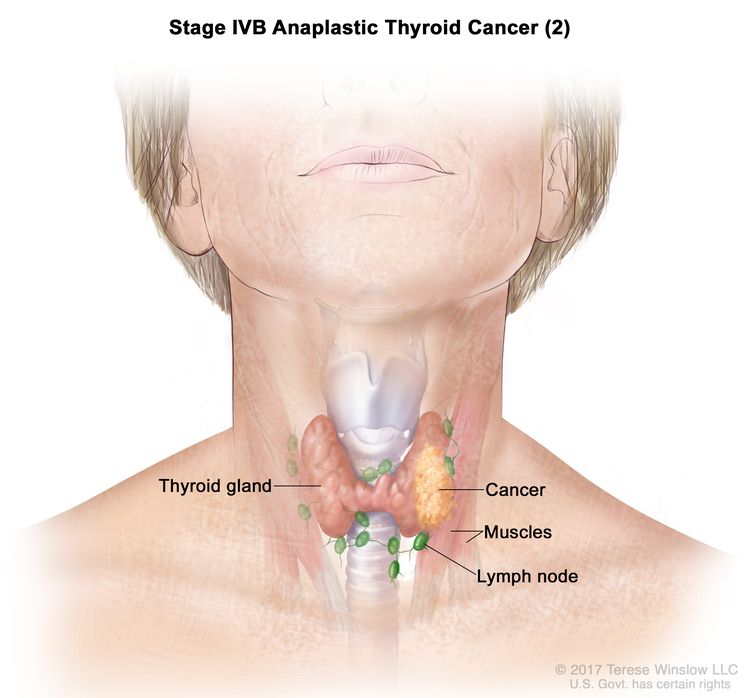

Thyroid Cancer Explore vol.3 no.2(2201 「Thyroid Cancer Expl Thyroid Cancer Treatment (PDQ®) - NCIの詳細情報

Thyroid Cancer Treatment (PDQ®) - NCI。Comparative Analysis of Metastatic Thyroid Carcinoma versus。The Role of Positron Emission Tomography/Computed Tomography。

ThyroidCancerExploreVol.3No

「ThyroidCancerExpl

Thyroid Cancer - Endotext - NCBI Bookshelf

Thyroid Cancer - Endotext - NCBI Bookshelf

■商品名■

ThyroidCancerExploreVol.3No

「ThyroidCancerExpl